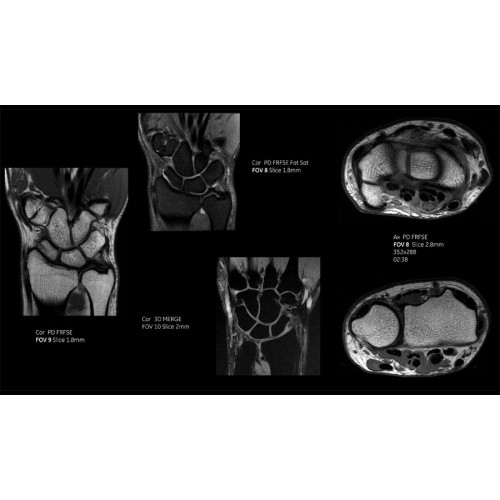

МРТ аппарат GE SIGNA Voyager 1.5T позволяет проводить полный спектр магнитно-резонансных исследований, включая нейровизуализацию, исследования опорно-двигательного аппарата, органов брюшной полости и малого таза, а также специализированные кардиологические программы.